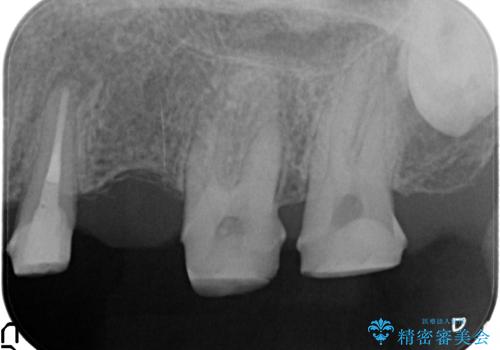

- 「老朽化し古くなった銀歯を白いものにやりかえたい。」と希望され来院されました。

銀歯の下には再発した虫歯やセメントの漏出が見られ、丁寧に除去したのちセラミックによるクラウン・ブリッジ補綴を行います。

適合や精度の悪い銀歯は、時間の経過とともに虫歯の再発リスクが高まります。